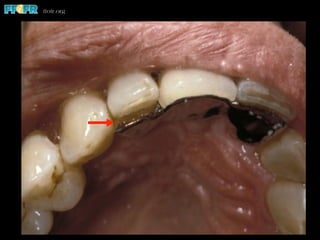

The lingual metal produces discoloration, particularly

through translucent portions of the abutment teeth

Tooth Discoloration

•  21% had incisal discoloration

Williams, 1984

•  Increases with time

4% after 7 years

25% after 10 years

37% after 15 years

Thayer, 1993

The lingual metalproduces discoloration, particularly through translucent portions of the abutment teeth